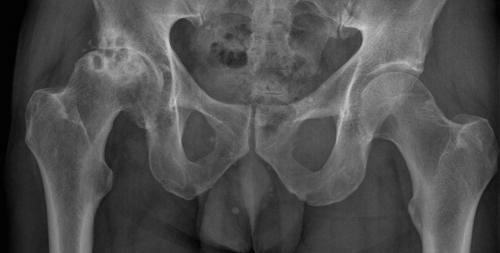

Коксартроз тазобедренного сустава 3 степени характеризуется запущенным протеканием заболевания: у больного наблюдается обширное поражение бедренной и тазовых костей. Человек не может нормально передвигаться и ходить без дополнительной опоры.

Коксартроз правого тазобедренного сустава 3-й степени (на снимке — слева).

Коксартроз 3 степени тазобедренного сустава может развиться, если больной в течение длительного времени не будет предпринимать никаких терапевтических действий по отношению к купированию начальных стадий заболевания. Существенно повышают риск запускания коксартроза несвоевременное обращение к врачу и бесконтрольная практика самолечения.

Слева поверхность головки тазобедренного сустава — в здоровом состоянии, справа — пораженная болезнью.